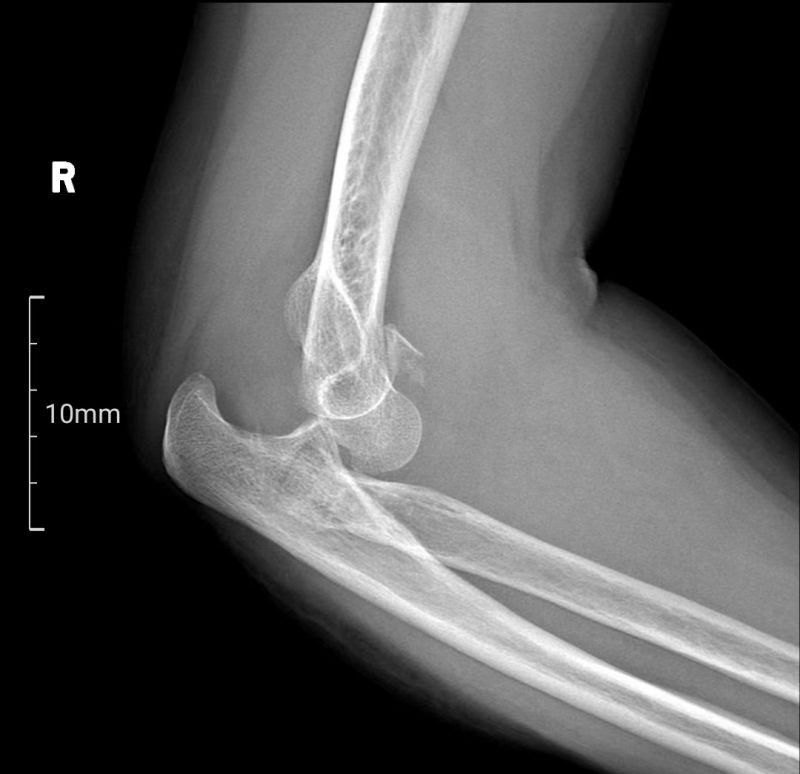

患者梁女士因不慎跌倒导致右肘关节疼痛并活动受限,经X线检查确诊为肘关节恐怖三联征。面对这一复杂病情,张立主任迅速组织科室医生及3D打印中心技术人员进行病例讨论,并决定采用3D打印桡骨小头置换术进行治疗。

肘关节恐怖三联征,作为一种复杂的肘关节骨折脱位类型,同时涉及肘关节后脱位、桡骨头骨折及尺骨冠突骨折三种损伤,其治疗难度极高。面对这一挑战,南溪山医院创伤骨科与手外科张立主任团队凭借其丰富的临床经验和前瞻性的技术视野,决定采用先进的3D打印技术为患者提供个性化治疗方案。